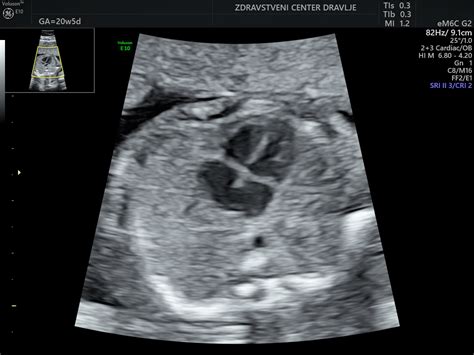

V 35. tednu nosečnosti je vaš dojenček že precej velik in težak. Trenutno meri okrog 46 centimetrov in tehta že več kot dva kilograma, pogosto med 2300 in 2700 grami, kar je povsem normalno. V tem času bo pridobival na teži po približno 200 do 250 gramov na teden, zato lahko med posameznimi dojenčki opazite znatne razlike v teži. Velikost vašega otroka je primerljiva z velikostjo ananasa.